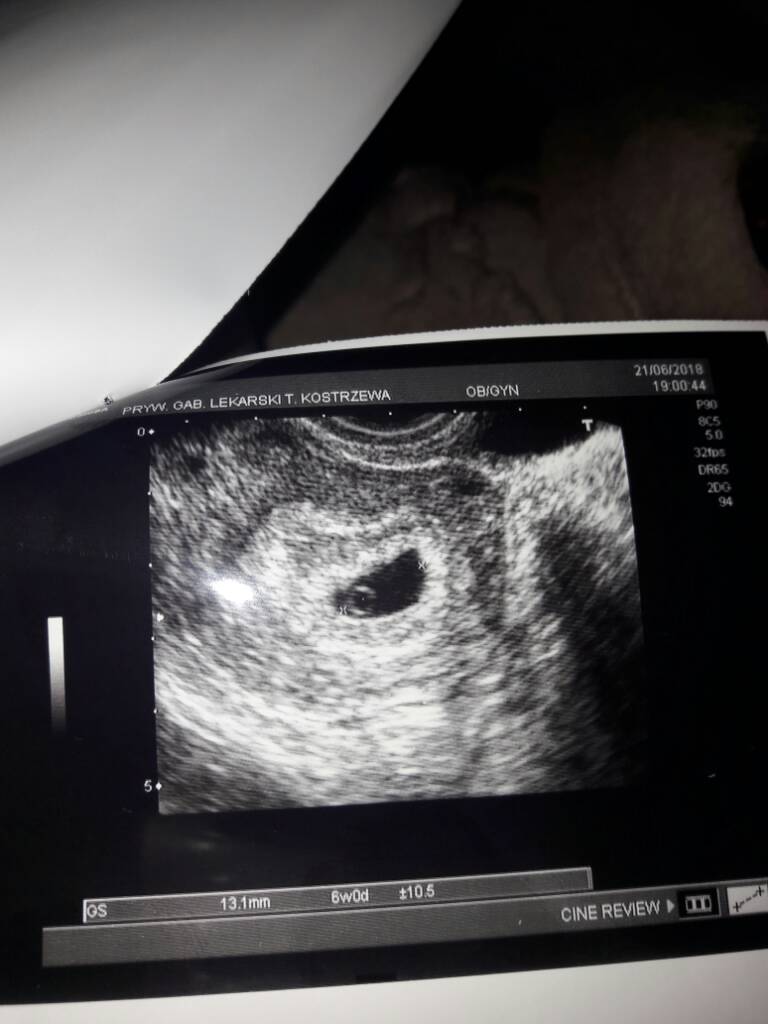

Pomyślcie o kobietach w Afryce, Indiach czy w ogóle tych które żyją dziko (np. plemiona w Ameryce Południowej). Pytanie: Gdzie jest największy współczynnik urodzeń? No właśnie - myślicie, że mama mieszkająca w Kongo bierze duphaston? Nic z tych rzeczy... Ona przez cała ciąże nie ma nawet USG, a często bywa i tak, że jeszcze 2/3 dni przed porodem idzie sama na boso do szpitala przez stepy i sawanny lub rodzi "w domu" - no właśnie w domu... czyt. glinianej chałupce, szałasie... Zobrazujcie sobie jej 9 miesięcy: odżywiania, higieny, warunków sanitarnych czy opieki medycznej. Dają kobitki radę? Dają. I z pewnością przez całą ciąże mniej się martwią i są bardziej szczęśliwe od nas - NAS czyli kobiet postępu, z dostępem do internetu, opieką medyczną i farmakologiczną... My mamy czyste mieszkania/domki, pieniądze, Rodziny, Mężów.. i wiedzę: w tym przypadku nieszczęsną wiedzę, która nas gryzie i kąsa od środka! Czasem lepiej nie wiedzieć i być spokojnym, niż wiedzieć, że istnieje np. jakaś listeria, która żerowała na Twojej parówce (hehe).